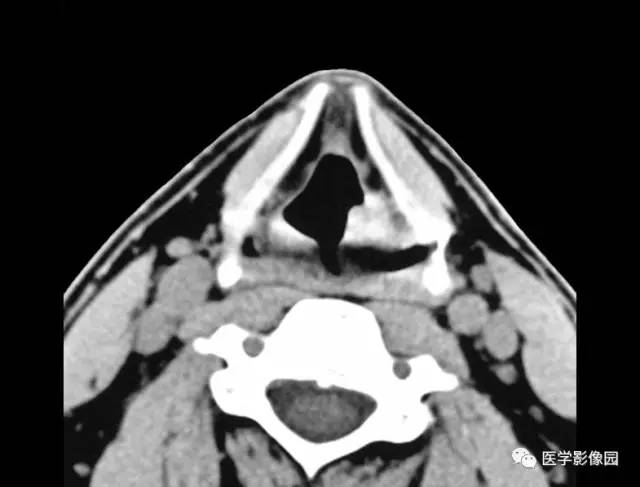

3.声带和室带可不规则增厚或形成软组织肿块(图3-5-10)。

图3-5-10 喉乳头状瘤A.B.

CT平扫见左侧室带后部局限性软组织肿块,

并向喉腔突入(↑),喉旁间隙显示清晰